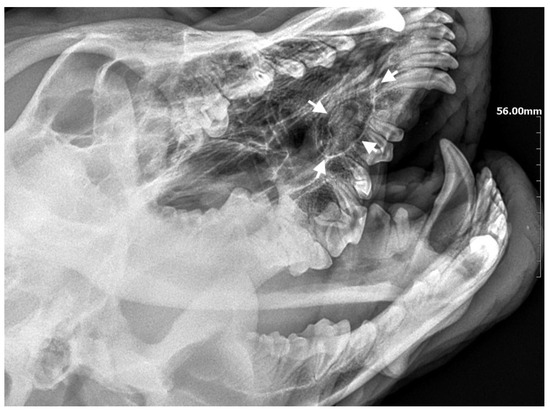

A 7-month-old male Rottweiler was referred for consultation because of severe swelling on the left side of the jaw, with a suspected jaw tumor. Clinical examination revealed no abnormalities in the aforementioned lymph glands and no soreness on palpation. Intraoral examination on the left side revealed severe asymmetry, with enlargement of the facial soft and hard tissues, an absence of permanent teeth, and buccal displacement of deciduous teeth. On the left side, rhinoscopic examination revealed normal anterior nostrils and a left nasal aperture with a lack of patency from the level of the nasal bony inlet to the posterior nostrils. A roentgenogram in the dorsal–ventral projection showed the presence of four ectopic teeth in the maxilla, with the formation of a dentigerous cyst (Figure 2). Using the CLP technique, the ectopic teeth were removed and the cyst walls were lanced. The bone loss caused by the cyst was 7.3 cm × 4.6 cm, and the jawbone left behind was too thin to provide a scaffold for the surrounding tissues and to ensure nasal cavity patency. From a 5 cm pellet of hydroxyapatite polymer material with curdlan previously soaked in saline (according to the manufacturer’s instructions), longitudinal flaps of 5 cm long, 1 cm wide, and 0.1–0.2 cm thick were cut and placed in the bony defect to strengthen the bony scaffolding of the jaw and nasal septum (Figure 3). The gingival flap was sutured with a single suture using 4-0 monofilament material. The first radiological follow-up was performed after 4 weeks, but due to the size of the defect and the size of the pellets of material used, the hydroxyapatite obscured the structures in the nasal cavity, preventing accurate assessment. A rhinoscopic examination revealed patency of the left nasal cavity. It was decided to conduct a radiological follow-up 6 months after the procedure, but the owner, for personal reasons, did not attend the follow-up appointment. After 12 months, another roentgenogram was performed, where a properly healed jawbone with closure of the cyst cavity could be observed. The nasal septum was formed properly, and the resulting bony scaffolding resulted in patency of the left nasal aperture, along with normal airflow on the left side (Figure 4).

Figure 2. X-ray in dorsal–ventral projection before surgery. On the left side, four ectopic teeth (marked with arrows) with the formation of a dentigerous cyst are visible.